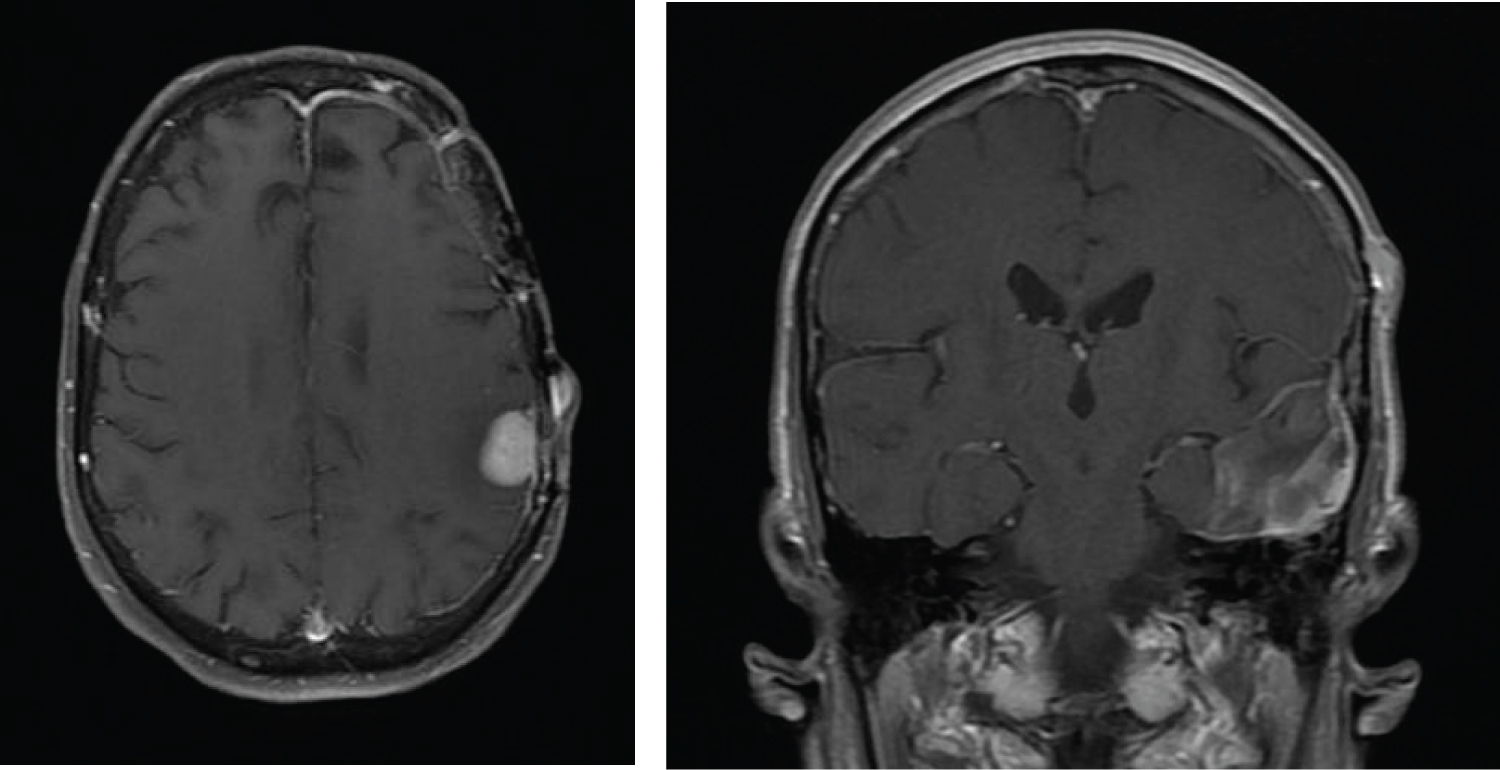

Two months after completion of her course of therapy, an MRI of the brain revealed progression of disease in the left temporal lobe and a new focus of signal abnormality in the medial right frontal lobe (Figure 6). Her performance status had markedly deteriorated and no further therapy was administered.

Figure 6: Axial and coronal contrast enhanced T1 images showing growth of the gliosarcoma in the left temporal lobe and development of a new mass in the right frontal lobe with dural contact. View Figure 6